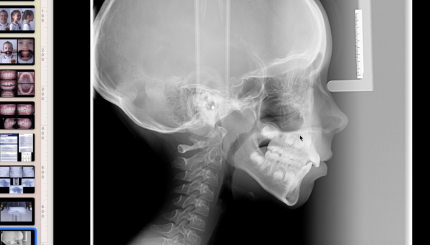

Класс 2 , низкий угол. Подход к лечению

Класс II, высокий угол. Подход к лечению.

Класс III, низкий и высокий угол. Подход к лечению

Клинический случай. Ребенок, II класс

Разбор кейса. MLD, ребенок, техника направленного роста